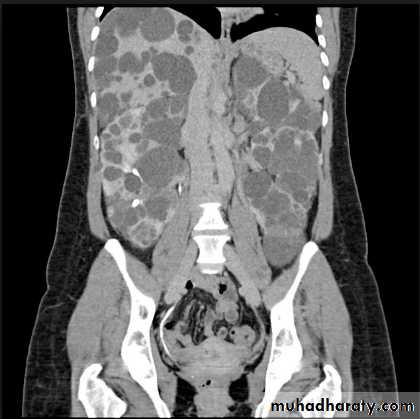

Poly cystic disease

Adult typePresent after the third decade of life , Familial.

Renal parenchyma is replaced by numerous cysts containing fluid , The cysts are of variable size ,

Clinically renal colic, loin mass , heamaturia and hypertension, Renal tissue interposed between the cysts after time dssimcted ended with renal failure

Almost bilateral.

Infantile type :

Usually affect liver, spleen and pancreas , Incompatible with life .I.V.U.

Bilateral Large kidney due to numerous small cysts

(1-2 mm size ).

- The out-line is not lobulated as in adult.

- I.V.U, may be normal.

- Nephrogram shows minute filling defects.